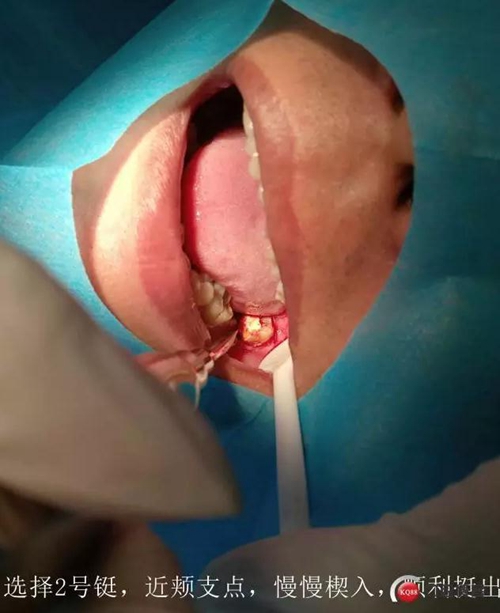

處置:38拔除

盡量囊腫刮除

討論:對于這種炎癥感染的囊腫,囊壁基本都不完整的,可視為頜骨囊腫開窗,進(jìn)行二期手術(shù),建議6個月后復(fù)查曲面。

如果強(qiáng)行一次完整取出,創(chuàng)傷會較大,神經(jīng)管損傷的可能性非常大,再者根尖區(qū)叩痛提示炎癥,不宜刺激

待頜骨骨壁恢復(fù)到離神經(jīng)管安全距離,再次手術(shù)比較安全。